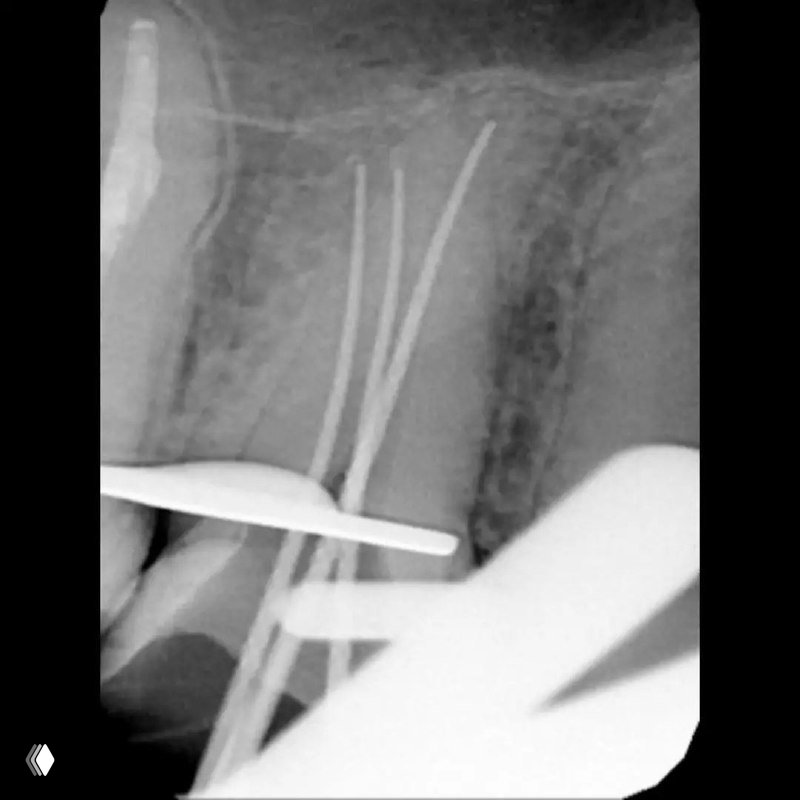

Распространенность: 1 премоляр вч - 3.2%, 2 премоляр вч - 0.4%

На что обратить внимание:

- классическую овальную полость доступа нужно немного расширить в области щёчных каналов в мезио-дистальном направлении

- проводить аккуратное расширение щёчных каналов, так как в области данных корней очень мало дентина (в моём случае расширение 25.04)